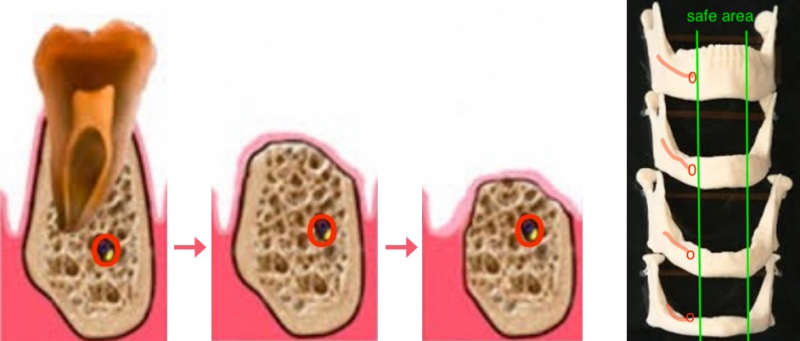

Dit is waarschijnlijk de meest essentiële overweging die we tijdens de planning dienen te maken. Indien de onderkaak zijn tanden verliest, dan resorbeert de kaak door rechtstreekse druk van het kauwen en de continue wrijvingen van de uitneembare prothese. In de onderkaak maken we steeds onderscheid tussen het gebied voor de alveolaire zenuw en het gebied erachter. Vooraan heeft de gevoelszenuw reeds de kaak verlaten en loopt die verder in de lip. Deze zenuw zorgt voor gevoel in de onderlip en beschadiging ervan is storend en dient vermeden. Praktisch gezien worden de implantaten geplaatst vooraan in de kaak en vòòr de zenuwuitgang, en meestal slechts uitzonderlijk meer achteraan.

Dr. Defrancq plaatst regelmatig implantaten met rechtstreekse loading in onderkaken die zelfs extreem weggekwijnd zijn (7 tot 10 mm hoogte!). Het is uiterst zeldzaam dat een onderkaak nood heeft aan botopbouw. Bij dergelijke ingrepen wordt bovendien de gevoelszenuw vaak geschonden met verlies van gevoel in de onderlip. Bovendien is een botopbouw in de onderkaak zeer gevoelig voor terug weg te kwijnen en te verdwijnen, waardoor de implantaten later te hoog uitsteken. Deze casus van de onderkaak illustreert dat we zelfs in de uiterst geresorbeerde gevallen nog implantaten plaatsen. Tijdens de planning is het van belang om grotere afstanden tussen de implantaten te respecteren en aldus kaakfracturen te vermijden. Vandaar ook het belang van de rechtstreekse loading met een vaste structuur, omdat deze dan fungeert als een spalk.